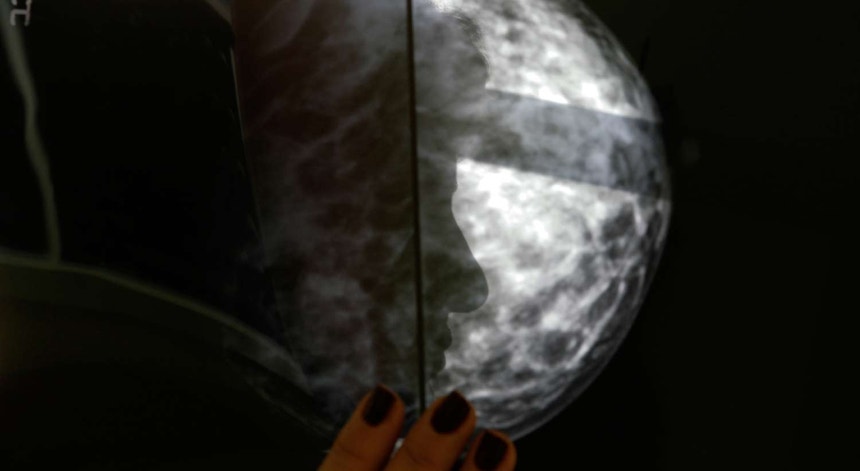

Um quarto dos portugueses entrevistados refere o cancro do pulmão como o tipo de doença oncológica que maior preocupação causa, logo seguido do cancro da mama, com 21%.

De todos os tipos de cancro o do pulmão é o mais receado pelos portugueses inquiridos neste estudo.

A presidente da associação Pulmonale encara sem surpresa que o cancro do pulmão seja considerado como o mais preocupante, já que "é o mais mortífero em todo o mundo e continua a ter uma evolução preocupante, com crescimento de casos nas mulheres".